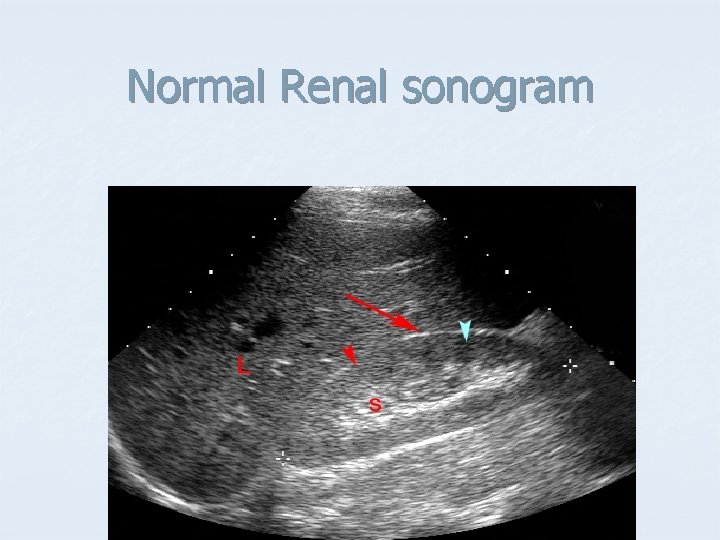

Normal Renal sonogram